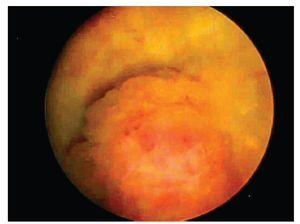

La cistoscopia posterior, demostró tumoraciones de las cuales se tomaron biopsias. Estas se encontraban en la línea media, desde la cúpula hacia el trígono, a uno o dos centímetros de distancia entre ellas y de color amarillento. Al corte se observó la salida del cuerpo de un parásito. (Imágenes 3, 4 y 5).

Imagen 3. Una de las tumoraciones vesicales durante la cistoscopia.